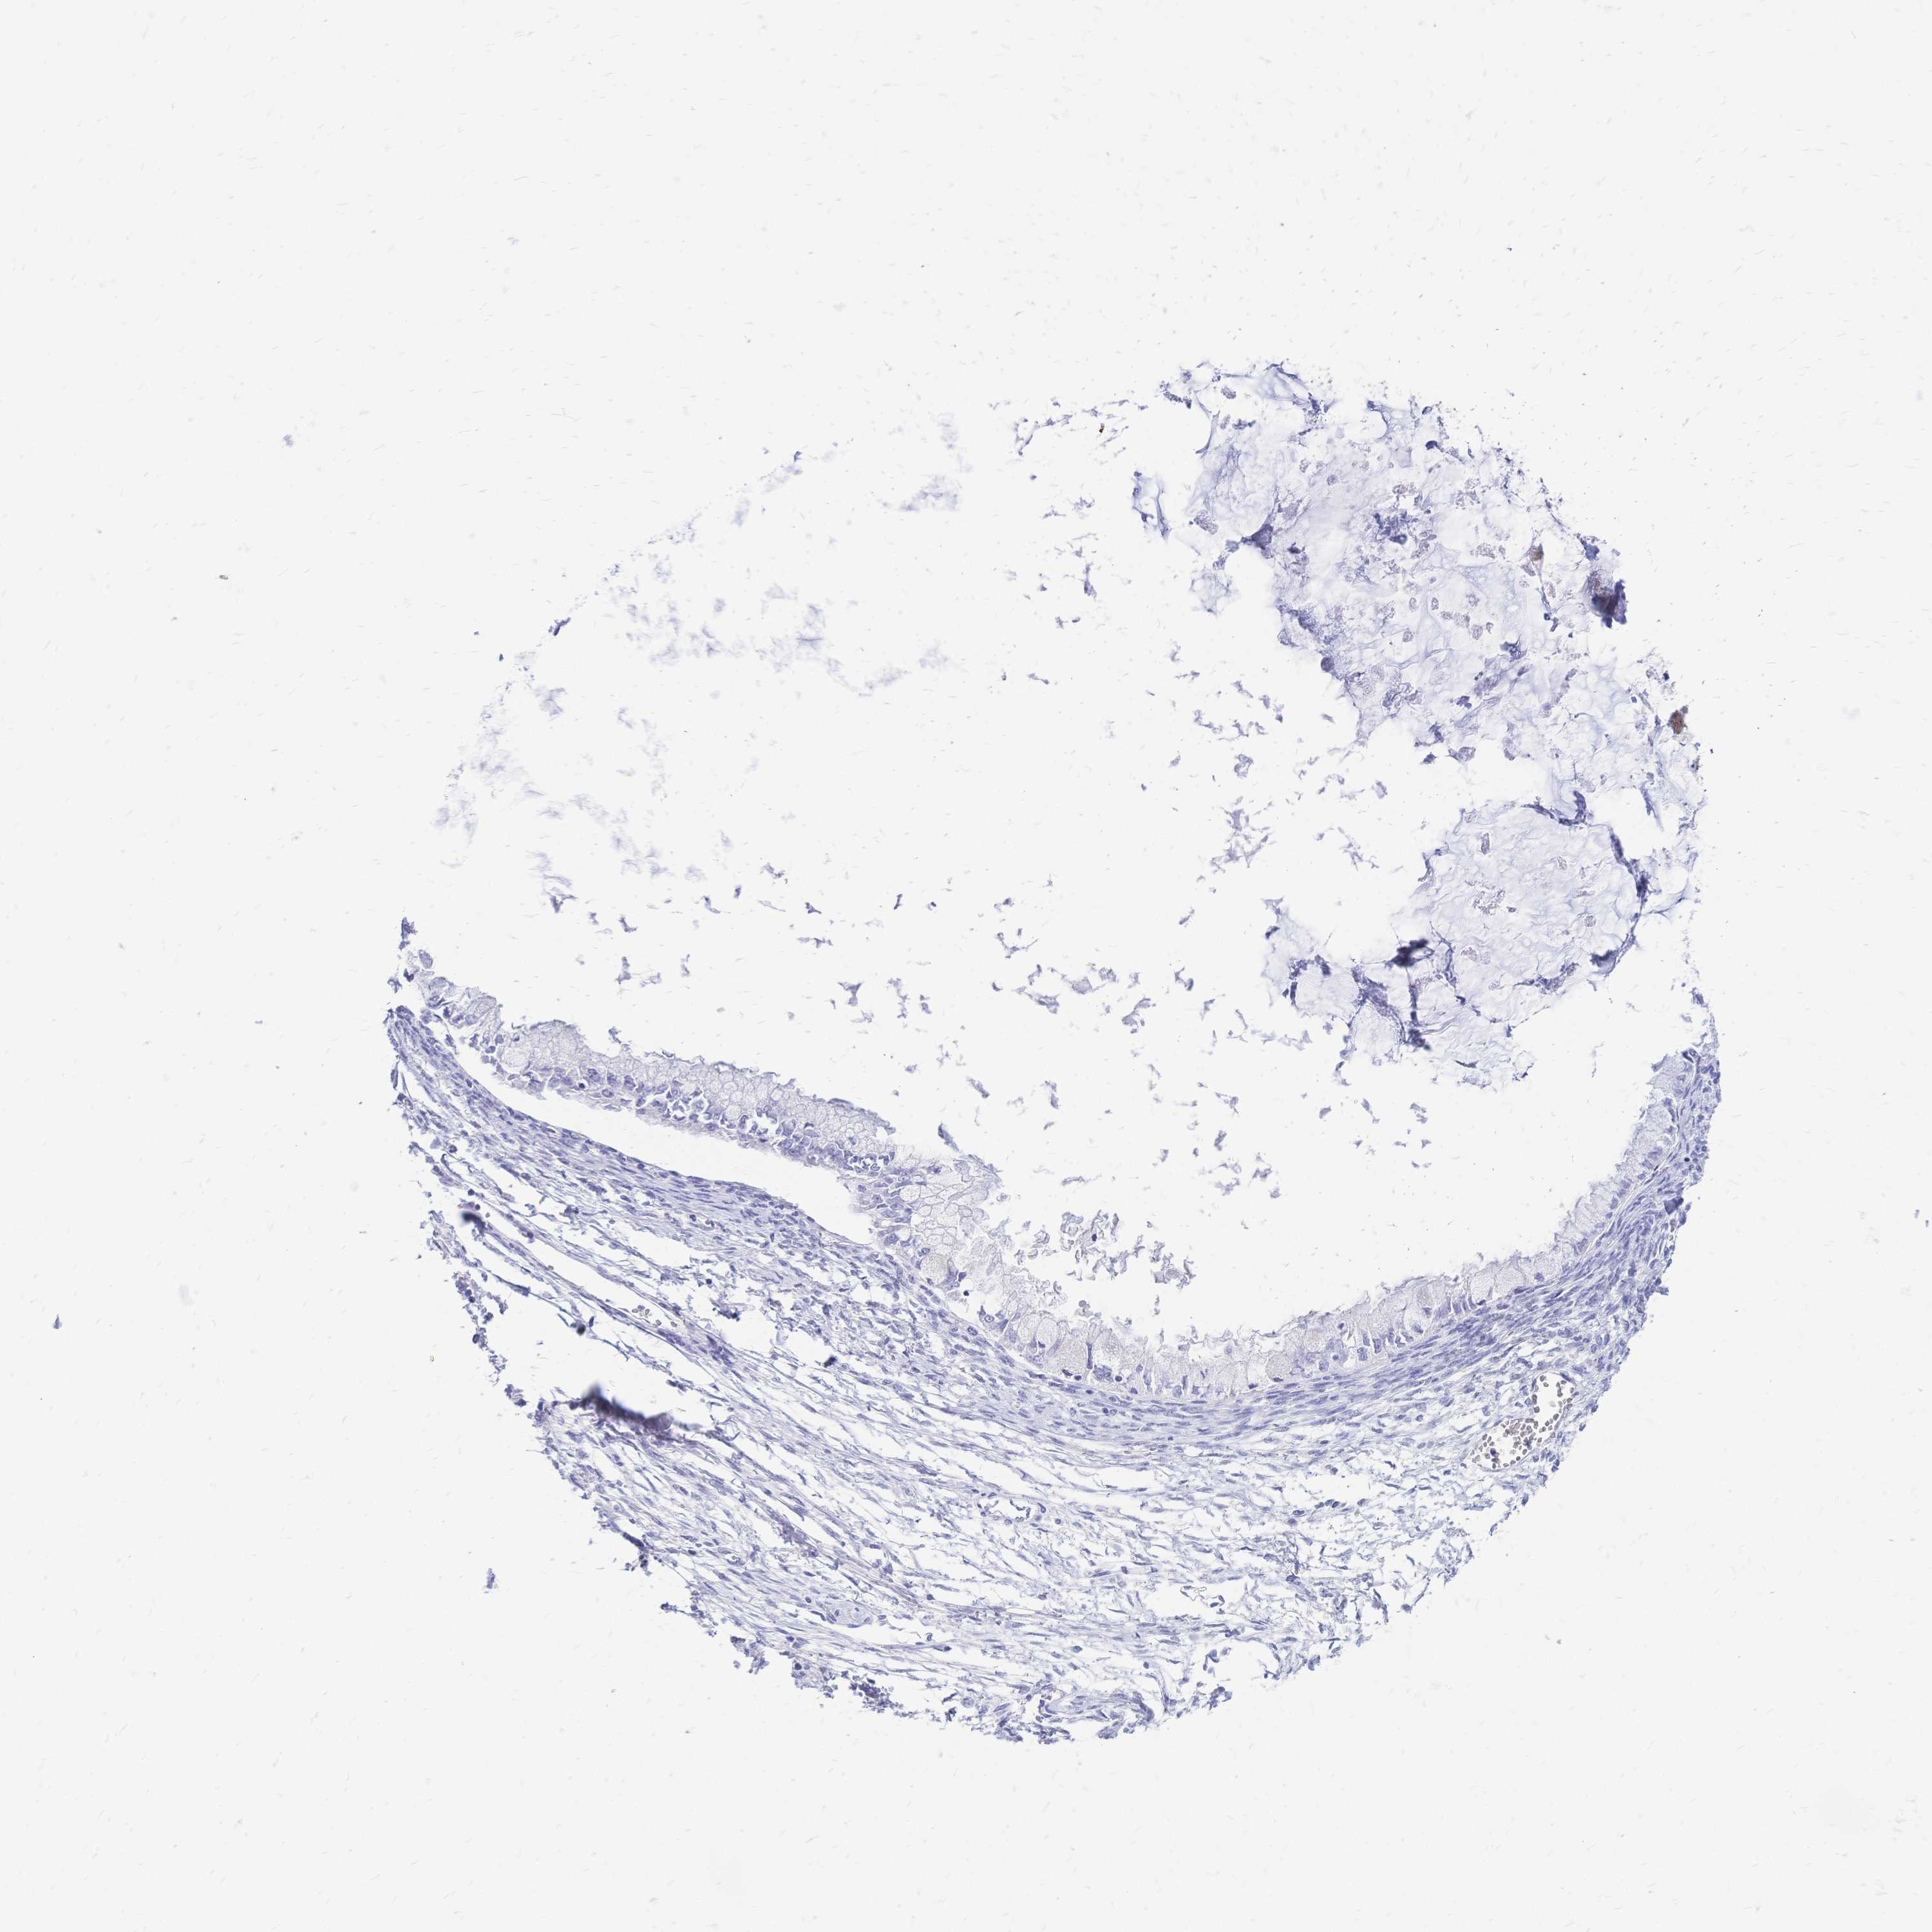

OVARIAN CANCER - Protein expressioni

A mouse-over function shows sample information and annotation data. Click on an image to view it in a full screen mode. Samples can be filtered based on level of antibody staining by selecting one or several of the following categories: high, medium, low and not detected. The assay and annotation is described here.

Note that samples used for immunohistochemistry by the Human Protein Atlas do not correspond to samples in the TCGA dataset.

Antibody stainingi

Antibody staining in the annotated cell types in the current human tissue is reported as not detected, low, medium, or high, based on conventional immunohistochemistry profiling in selected tissues. This score is based on the combination of the staining intensity and fraction of stained cells.

Each image is clickable and will lead to virtual microscopy that enables deeper exploration of all samples and also displays staining intensity scores, fraction scores and subcellular localization as well as patient and tissue information for each sample.

Antibody HPA056614

Staining

High

Medium

Low

Not detected

Intensity

Strong

Moderate

Weak

Negative

Quantity

>75%

75%-25%

<25%

None

Location

Nuclear

Cytoplasmic/membranous

Cytoplasmic/membranous,nuclear

Cystadenocarcinoma, serous, NOS

Cystadenocarcinoma, mucinous, NOS

Carcinoma, endometroid